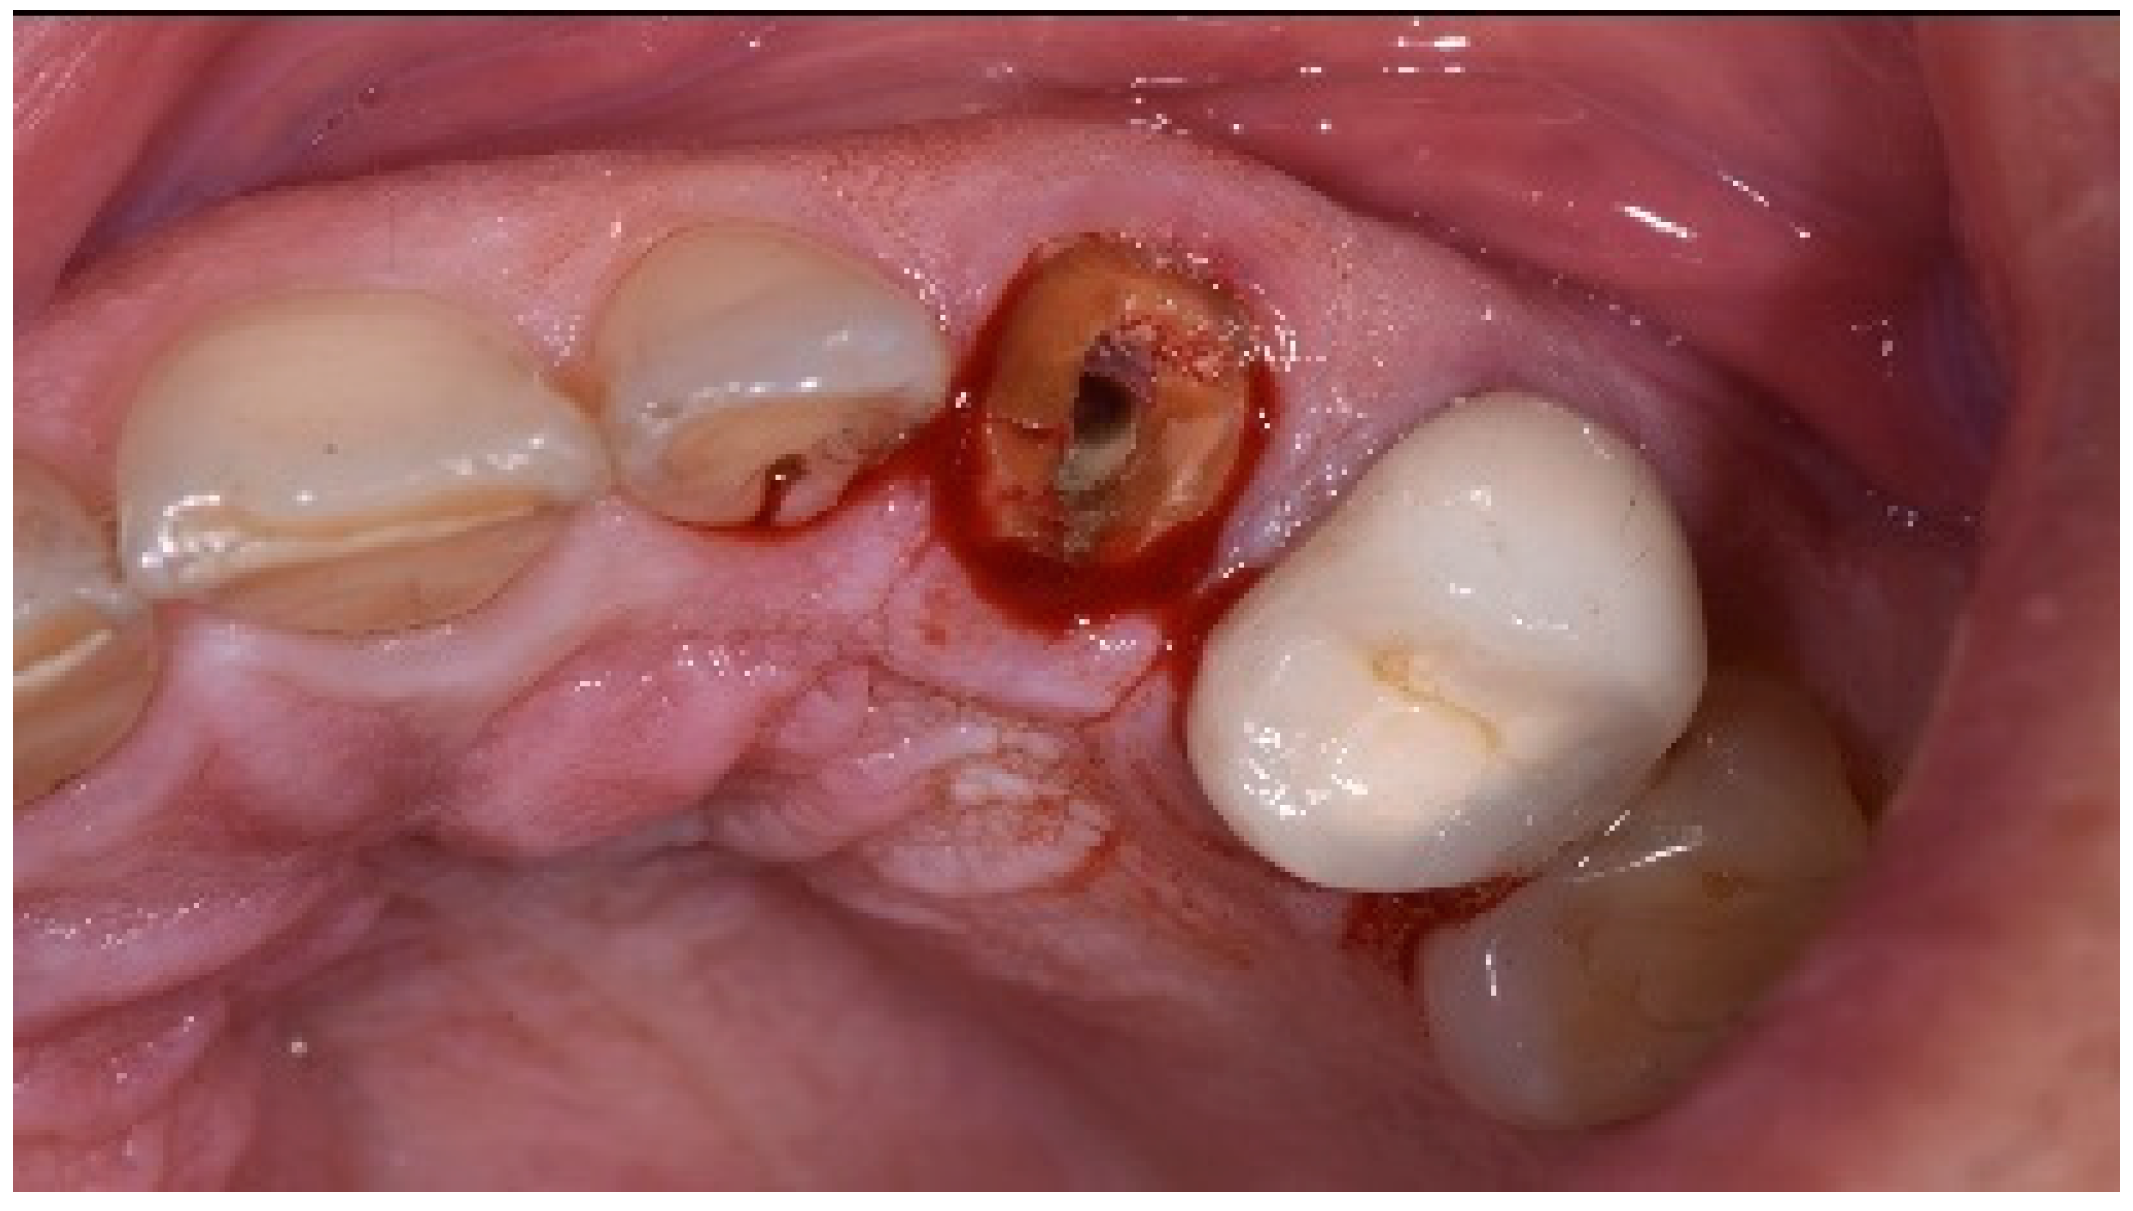

A 51-year-old male in good health and a non-smoker presented to our clinic with a fractured lateral incisor. Clinical and radiographic examination deemed to tooth non-restorable (Figure 8). The treatment plan proposed was to extract the tooth and place an immediate implant with simultaneous bone regeneration of the buccal wall.

Figure 8.

Clinical view of implant placement.

The patient accepted the proposed treatment plan. The preoperative surgical protocol described in patient 1 was followed. An L-shaped aesthetic flap design was chosen to treat this case. The flap started with an incision extending from the distal line angle of the central incisor to the mesial line angle of the canine. A vertical incision was carried out past the mucogingival junction, followed by the elevation of a full-thickness flap. The remaining tooth root was extracted, maintaining the existing facial bone (Figure 9).

Figure 9.

Clinical view of implant replacing.